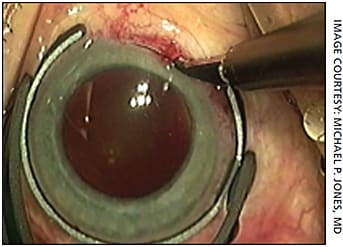

Patients who have a total corneal astigmatism of less than 0.75 D can be dealt with using corneal incisions. Several nomograms are available for surgeons to follow, including LRIcalculator.com for handcut incisions and LaserArcs.com for femto-cut arcuate incisions. Femto-cut arcuate incisions have the advantage of being more predictable than handcut5 due to accuracy of placement and uniformity of depth. Platforms like Lensar or a Verion-coupled LenSx account for cyclorotation for added predictability. Also, femto incisions can be left closed and then opened at a later date to titrate any residual astigmatism as needed.